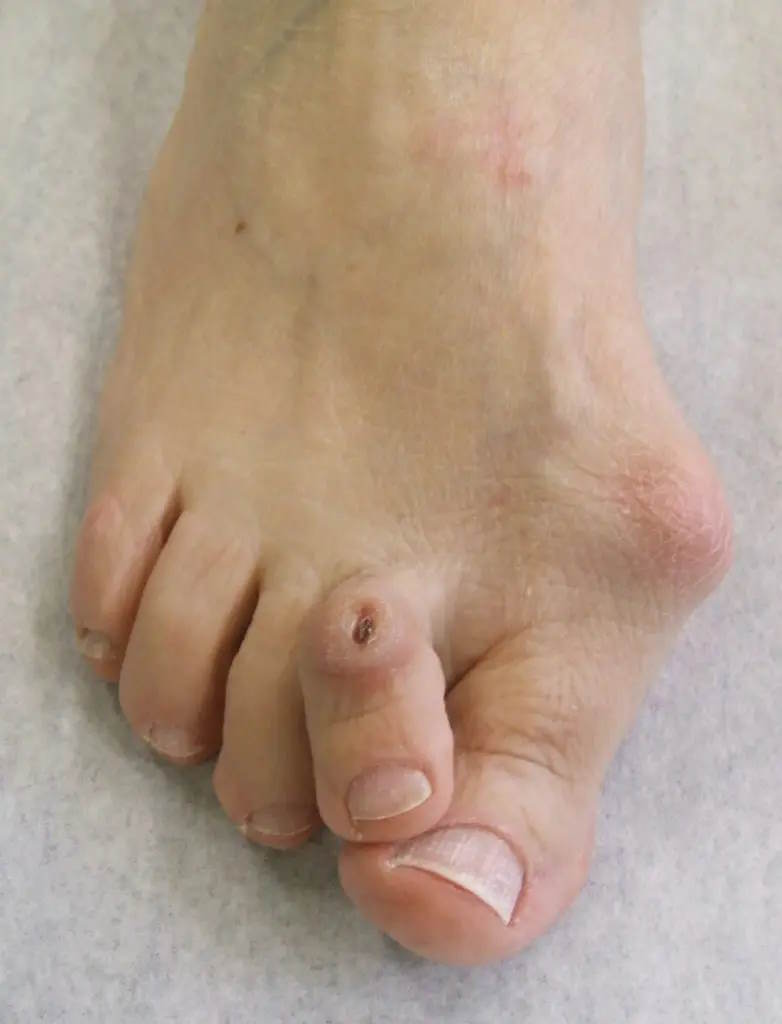

Die Valgusstellung der Großzehe kann zu einer Verdrängung der benachbarten Zehen führen. Das Ausweichen der Kleinzehen geht häufig mit der Ausbildung einer Hammerzehe oder Krallenzehe einher.

Hallux valgus mit Verdrängung der 2. Zehe